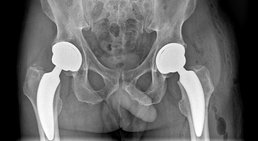

Endoprothetik Hüfte

Minimal-invasive Hüftendoprothetik/Minimal-invasiver Hüftgelenksersatz Minimalinvasive Operationswege (Zugänge) haben sich bei der Implantation eines künstlichen Hüftgelenks bewährt, da sie besonders gewebeschonend sind. Die Muskulatur wird dabei lediglich zur Seite geh...